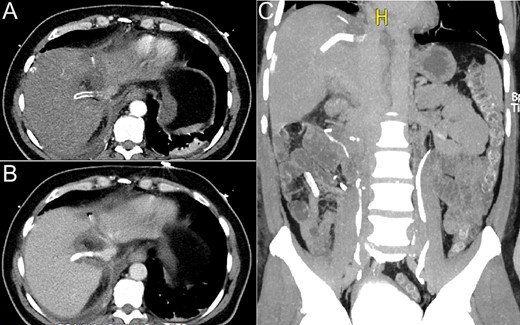

The parenchyma was transected using bipolar forceps under intermittent Pringle manoeuvre [7]. Transection started at the middle hepatic vein until it was released from the tumour, and proceeded posteriorly to release the tumour from the IVC. Right hepatic vein was cut close to the IVC and the IVC was sutured. The remaining parenchyma was transected and the right hepatic vein was skeletonized for a length of 1 cm to allow graft placement (Fig. 2). Subsequently, the open end of the graft was anastomosed in a standard manner to the IVC (Fig. 3).

(A) Right hepatic vein sutured close to the IVC. (B) Middle hepatic vein freed from the tumour. (C) Right hepatic vein within the transected area skeletonized for 1 cm. (D) Retrohepatic IVC, area to be anastomosed to one end of the graft. (E) Segment 8 with the tumour.